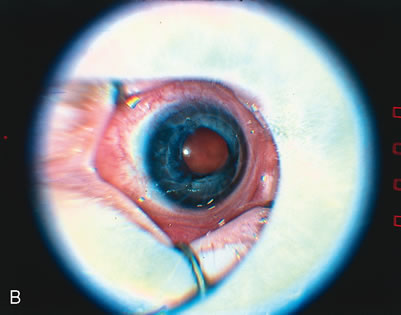

The technique of open-sky vitrectomy was pioneered by Schepens77 and Hirose and others,78and was modified by Hirose and associates73 and Tasman and colleagues (Fig. 10).74 Improvements in closed vitrectomy techniques have now almost eliminated the need for open-sky vitrectomies in the treatment of advanced ROP. If corneal opacification is present, corneal button removal followed by placement of a temporary keratoprothesis can be used to provide a closed working environment. This combined procedure allows excellent visualization of the anterior retina during bimanual surgery while providing a controlled intraocular pressure.

Fig. 10. A. Preoperative ROP stage V. B. Postoperative after open sky technique (Courtesy of William Tasman, MD, Philadelphia, PA)